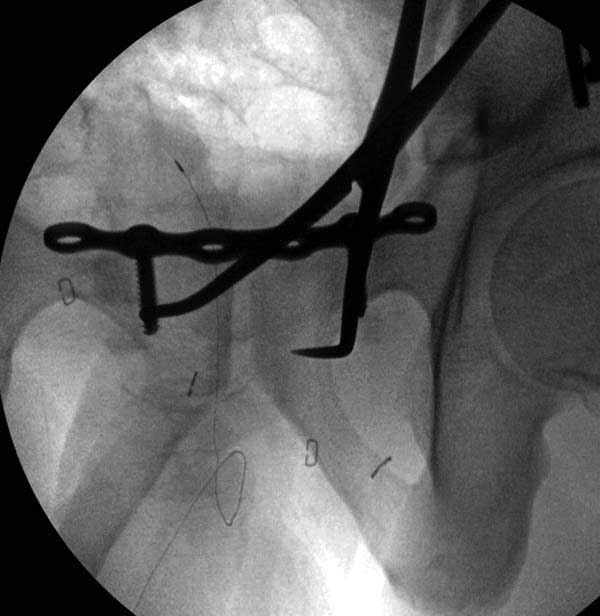

Представлены снимки техники проведения стержней. Через место прикрепления прямой мышцы в Inferior Iliac Spine в направления вырезки создается жесткость. Weber clamp изнутри таза для репозиции, и фиксация после репозиции перелома крыла подвздошной кости. Наружный аппарат удален, нагрузка предполагается через два месяца.

Реконструктивные пластины слабые, и для усиления необходимо установить дополнительную верхнюю пластину или оставить передний наружный фиксатор. Предпочтительным для фиксации считаю специальную для симфиза жесткую пластину из набора Joel Matta (Stryker), которая лучше, чем остальные, создает жесткость.